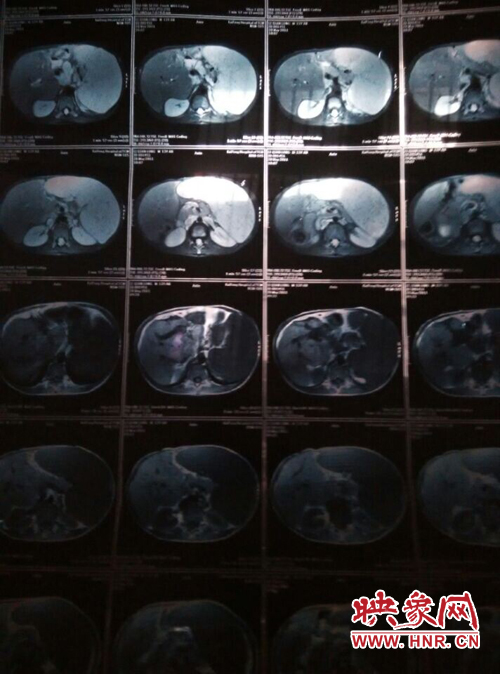

映象網(wǎng)商丘訊(記者 曾巖 代艷)他是一個花季少年,兩歲半時患上怪病,經(jīng)過漫長的求醫(yī)之路查出是肝脾腫大,十幾年的看病之路,花了幾十萬,非但沒有醫(yī)好他的病,讓這個原本就貧困的家庭雪上加霜。

他叫李乾龍,今年16歲,家住寧陵縣城郊鄉(xiāng)李莊村,家里有四口人,目前在寧陵縣黨校就讀上高一,他一邊上學一邊看病,十幾年來,他們跑遍了大小醫(yī)院,卻一直沒查出他的病因。16歲的他發(fā)育的還沒有13歲的弟弟高,肚子大的像個皮球,經(jīng)常身體發(fā)熱,全身無力,因為沒錢去大醫(yī)院檢查治療只得在家保守治療。